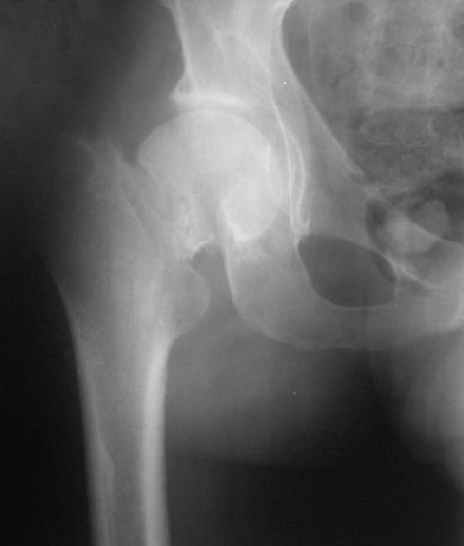

Глубокоуважаемые коллеги,Вчера обратился мужчина 31 г. Травма 2 месяца назад, лечился в одном из городов области. Был не самый тяжелый перелом таза, который проведен консервативно. С ним и связывали невозможность поднять ногу.

Однако на сегодняшнем снимке обнаружился перелом шейки бедра. Больной уже ходитс частичной нагрузкой. Учитывая срок и картину на снимке, что предпринять? У нас предложены варианты 1)не оперировать, 2)закрыто 2 спонгиозных винта, 3)вальгизирующая остеотомия. Эндопротез как-то даже в список включать пока не хочется. Какие есть соображения? Что из перечисленного или что-то другое выбрать и почему? Заранее спасибо.

Dear colleagues,A male 31 years old treated elsewhere after not severe pelvic fracture, was managed non operatively. So the injury looked as a reason of his inability to elevate the leg. However at the recent x-rays the neck fractire was found. The patient already has been walking with partial weight-bearing.Looking at the x-rays and the time since the injury, what is the optimal treatment for now? We discussed 1)leave as is, 2)2 cancellows screws as is, 3)valgus osteotomy. Total hip replacement looks unnecessary yet.What is your opinion? Which option from the listed or something else should be preferred and why?THX in advance.